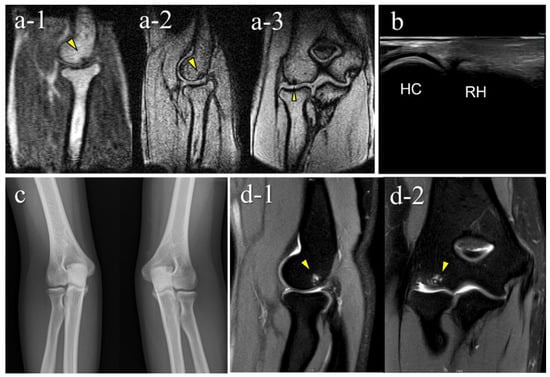

Figure 7. An OCD case during the healing process (Case 5): Mobile MRI (+), US (-). (a) Mobile MR image of T1WI sagittal: Mobile MRI showing signal intensity changes reflecting bone marrow edema in the anterior humeral capitellum; (b) US image of the posterior longitudinal view: b-1, the central posterior; b-2, the lateral posterior: US images showing no significant findings in the central posterior longitudinal view. However, there was a subchondral bone discontinuity in the lateral posterior longitudinal view; (c) X-p AP view with elbow 45° flexed: X-p 45° showing delayed ossification in the lateral capitellum, observed in incomplete healing OCD cases []. In addition, there was a translucent area in the central capitellum, stage I-OCD; (d) CT images: d-1, sagittal image; d-2, coronal image; d-3, axial image: CT images showing the subchondral bone sclerosis, and the surface was almost repaired. White arrowheads: delayed ossification.